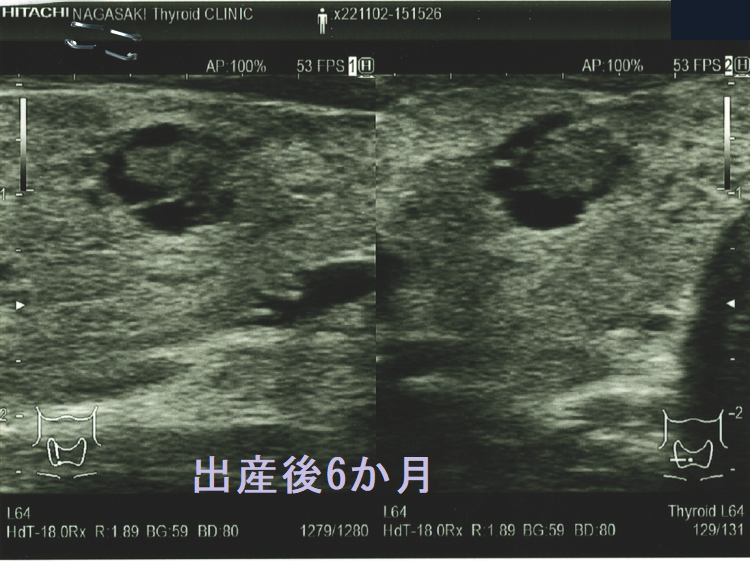

隈病院の統計では妊娠中、甲状腺微小乳頭癌の44.4%がサイズが増大するとのことです[Thyroid. 2014 May;24(5):840-4.]。もちろん、甲状腺刺激作用を持つhCGの影響が大きいと思われます[J Clin Endocrinol Metab. 1991 Oct;73(4):824-31.]が、あまり気持ちの良いものではありません。

隈病院の報告によると、50人の甲状腺微小乳頭癌妊婦のうち、

- 8%が3 mm以上の増大

- その半分が分娩後に手術

- もう半分は分娩後に甲状腺微小乳頭癌の増大が止まったため、積極的非手術経過観察(アクティブ サーベイランス)を再開

になったそうです[Thyroid. 2016 Jan;26(1):156-60.]。

妊娠前の甲状腺超音波(エコー)検査ではなかったのに、出産後に甲状腺微小乳頭癌が見つかるケースがあります。甲状腺刺激作用を持つhCG[J Clin Endocrinol Metab. 1991 Oct;73(4):824-31.][Obstet Gynecol. 1990 May;75(5):775-8.]が、隠れていた甲状腺乳頭癌細胞の増殖を促進した可能性が考えられます。